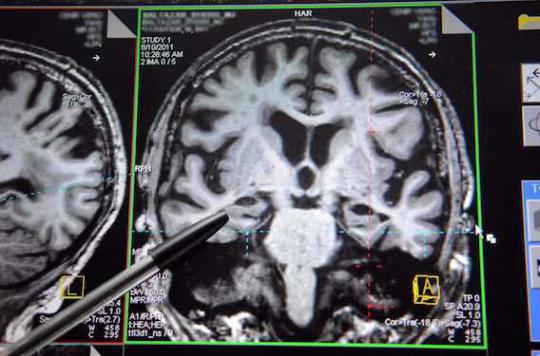

Diagnostic : un dispositif inspiré de la sismologie pour « palper » le cerveau

Des chercheurs français ont développé une technique pour mieux diagnostiquer les maladies cérébrales, de manière non invasive.

- DURAND FLORENCE/SIPA

S’inspirer de la sismologie pour diagnostiquer les maladies cérébrales et dégénératives. C’est le pari fait par Stéfan Catheline et son équipe de l’unité INSERM« Applications des ultrasons à la thérapie ». Les chercheurs ont élaboré une nouvelle méthode d’imagerie médicale qui permet d’analyser l’élasticité des tissus cérébraux, et de détecter ainsi des changements qui seraient synonymes de tumeurs ou de dégénération cérébrale.

Dans le cas du cerveau, protégé par la boîte crânienne et le liquide céphalo-rachidien, la palpation et l'élastographie posent problème. L’accès direct des médecins au cerveau est restreint, à moins de pratiquer une chirurgie à crâne ouvert. Une approche très invasive que l’état du patient ne justifie pas toujours.